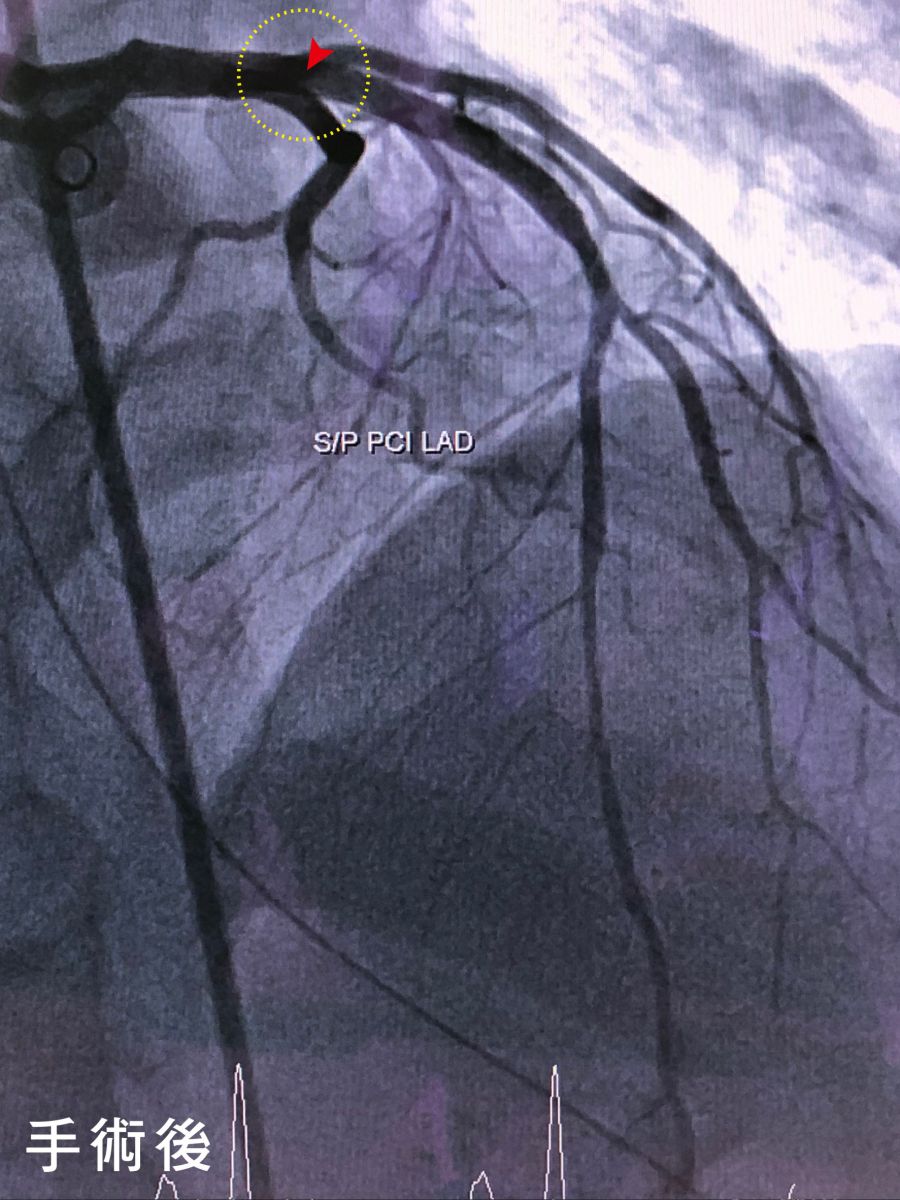

圖:紅圈處即為梗塞位置手術前後差異

光田綜合醫院重症醫學暨心臟內科醫師柯君樺表示,病人到院檢查發現心臟左前降枝冠狀動脈完全堵塞,右冠狀動脈血栓,經心臟內科黃世忠主任醫師率領之心導管團隊快速搶救在50分鐘內成功完成左前降枝冠狀動脈疏通手術、穩定心血管狀況,續進入低溫治療後逐漸清醒,再經2周治療檢查右冠狀動脈血栓也已消失,未來持續復健、服藥和回診追蹤即可。